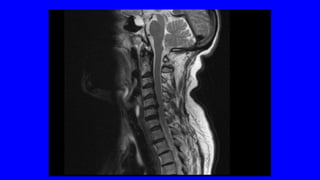

DOLOR CRÓNICO

OSTEOARTICULAR

DOLOR NOCIEPTIVO SOMÁTICO

•ES EL MÁS FRECUENTE

LA ARTROSIS